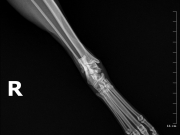

Į veterinarijos kliniką žmonės atvežė automobilio nutrenktą katinuką. Atlikus rentgeną paaiškėjo, kad abi užpakalinės kojos per sąnarius suknežintos į skeveldras. Vienos kojos raiščiai nutraukti. Apžiūrėjusi nuotraukas ir įvertinusi skeveldrinius lūžius chirurgė informavo kad operacija bus itin sudėtinga ir brangi. Vienu metu ji galėtų atlikti tik vienos kojytės operaciją, o po savaitės ar daugiau žiūrint kokia gyvūno būklė galės operuoti antrą. Visa tą laiką katinukas bus klinikos stacionare.

Chirurgė perspėjo kad operacija, gydymas ir pooperacine slauga klinikoje kainuos tikrai pakankamai daug nes užtruks mėnesį ar net daugiau laiko.